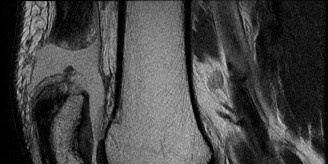

The role of nonoperative treatment in ACL injuries? CASE 3 A 44-year-old man slips while dancing at a wedding. With the help of his spouse, he is able to get home safely, but the next morning he has difficulty standing on his left leg. His knee is swollen, with little pain. If he gets on his feet, he is able to get around the house, but he is unable to go up or down stairs and feels unsteady on his feet.

His examination reveals a large swollen knee, held at 30 degrees of knee flexion. He has little pain with passive flexion or extension and no tenderness to palpation. He is unable to actively extend his leg when supine. When lying on his right side, however, he can make his left leg straight.

What is the most likely diagnosis?

The correct answer is (A). An MRI of a quadriceps tendon rupture is demonstrated in Figure 9–3. The inability to extend the leg against gravity is most consistent with an injury to the extensor mechanism. The absence of tenderness on palpation and pain with passive motion makes a patella fracture unlikely. A transient patella dislocation can result in swelling but does not prevent a straight-leg raise. Placing the patient in the lateral decubitus position eliminates gravity as a resisting force.

Figure 9–3